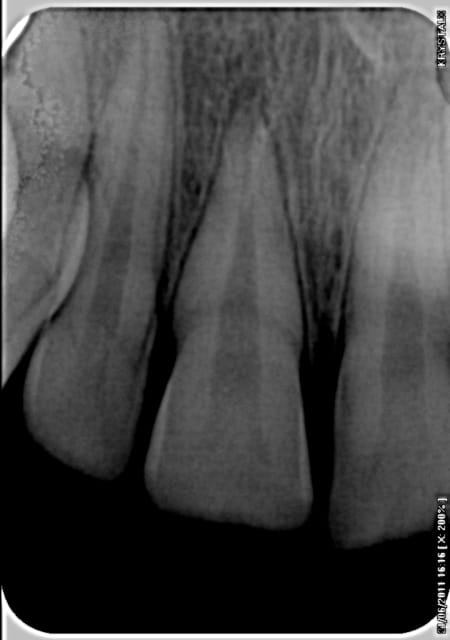

Je viens de recevoir un jeune patient, 13 ans, qui s'est pris une balle de basket ce matin.

La 11 a donc pris cher, elle s'est reculée de 2 mm côté palatin, empechant toute fermeture buccale.

Comme vous pouvez le voir sur la radio, on pourrait penser que la dent s'est cassée; mais je bosse avec un confrère au cabinet, et il me dit que des fois ça peut se remettre malgré tout d'une part, et que d'autre part, la "fracture visible à la radio" n'est des fois qu'un artefact et que la dent se soit simplement reculée SANS fracture.